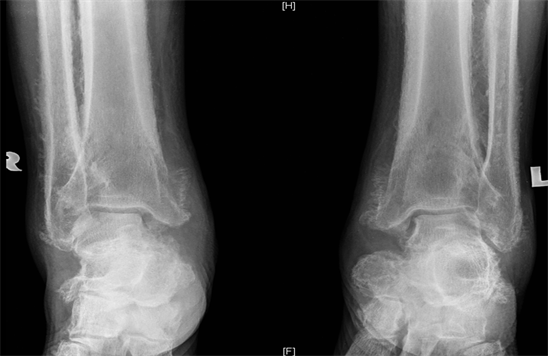

X ray of the hands showed prominence of soft tissue and enlargement of the proximal, middle and distal phalanges with cortical thickening (Figure 7). There was also periosteal reaction with bone formation affecting his long bones (Figure 8).

Figure 8. X ray of both legs shows cortical thickening with periosteal reaction with shaggy, ill-defined bony proliferation involving diaphysis, metaphysis and epiphysis.

The characteristic radiological features are bilateral and symmetrical cortical thickening and long bone periostitis. Periosteal reaction is irregular and involves the diaphysis and often extends to the epiphysis. There is preservation of joint space with absence of erosions or periarticular osteopenia [11] .